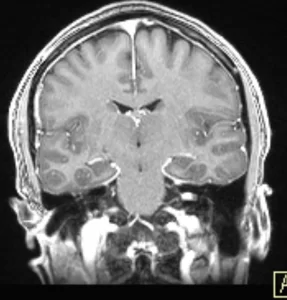

Ασθενής άνδρας, 39 ετών ο οποίος παρουσίασε έκπτωση ακοής αριστερά, διαγνώστηκε με μικρή ενδοκαναλική (δηλ. εντός του έσω ακουστικού πόρου) εξεργασία σύστοιχα, συμβατή με μικρό ακουστικό νευρίνωμα (αιθουσαίο σβάννωμα). Ο επανέλεγχος με μαγνητική τομογραφία λιθοειδών ανέδειξε μικρή (1χιλ) αύξηση του μεγέθους του νευρινώματος. Αναφερόμενος άτυπος σπασμός ημιπροσώπου αριστερά.